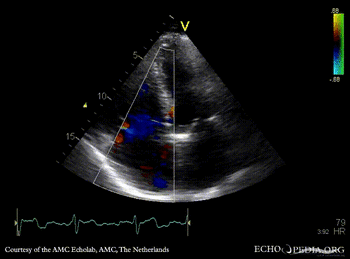

Systolic flow reversal in hepatic veins

A4CH with Color Dopler, severe tricuspid regurgitation Continuous-wave signal of tricuspid regurgitation